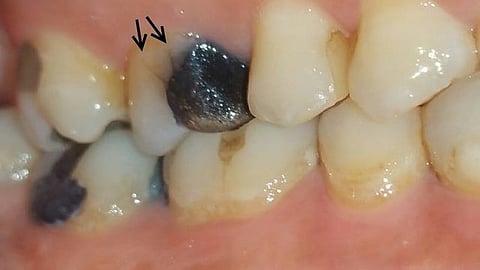

Fractured cusp: A crack is formed around a dental restoration

Visual examination: One should inspect for large restoration, steep cusps, wear facets, cracked restoration, etc